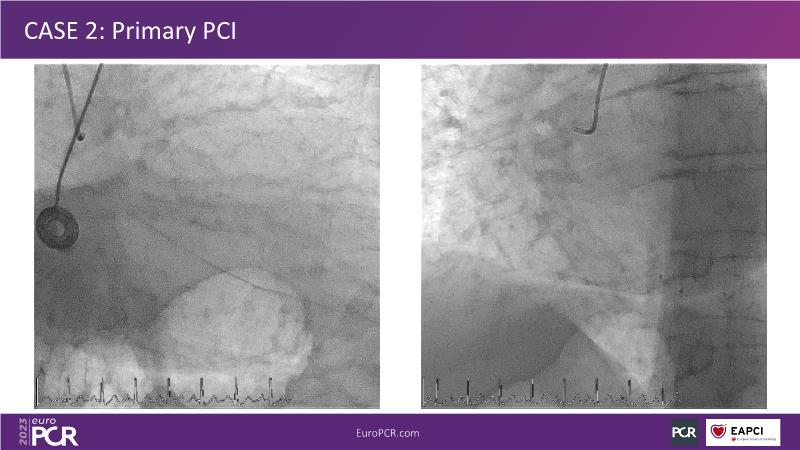

• To know why and how a fusion coating of DES+DCB stent platform is effective for the treatment of cardiovascular disease in diabetes mellitus patients via case presentations

• To understand why you can count on customised drug delivery platform of DES+DCB in complex settings with imaging-based evidence through case presentations